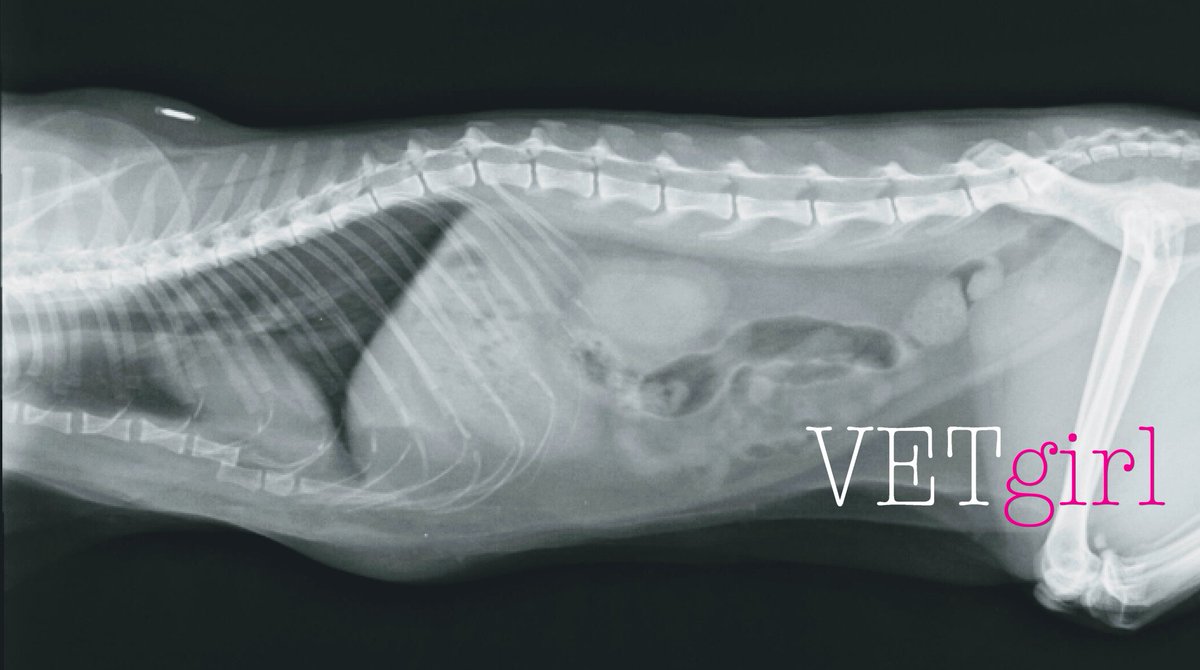

@VetGirlOnTheRun

VETgirl

6 years

Thanks to Amanda for sending in this x-ray! We suspect there was trauma. Can you spot the abnormality? COMMENT BELOW! Answer at 6pm Eastern! #VETgirl #VetMed #Veterinary #VetTech #CE